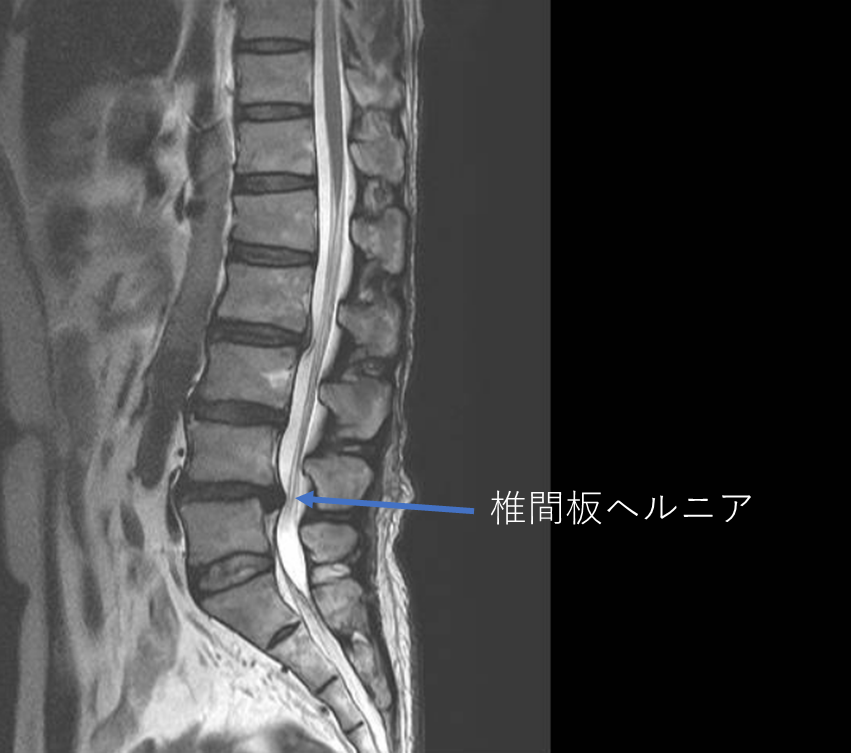

画像及び所見について

- L2/3,3/4,4/5-椎間板変性

- L4/5-椎間板ヘルニア

以上の事が画像上認められます。

・L4/5-椎間板ヘルニアを認め、歩行困難となった要因の可能性が一番高い

・L2/3,3/4-椎間板変性を認め、主訴の可能性と予防的側面から